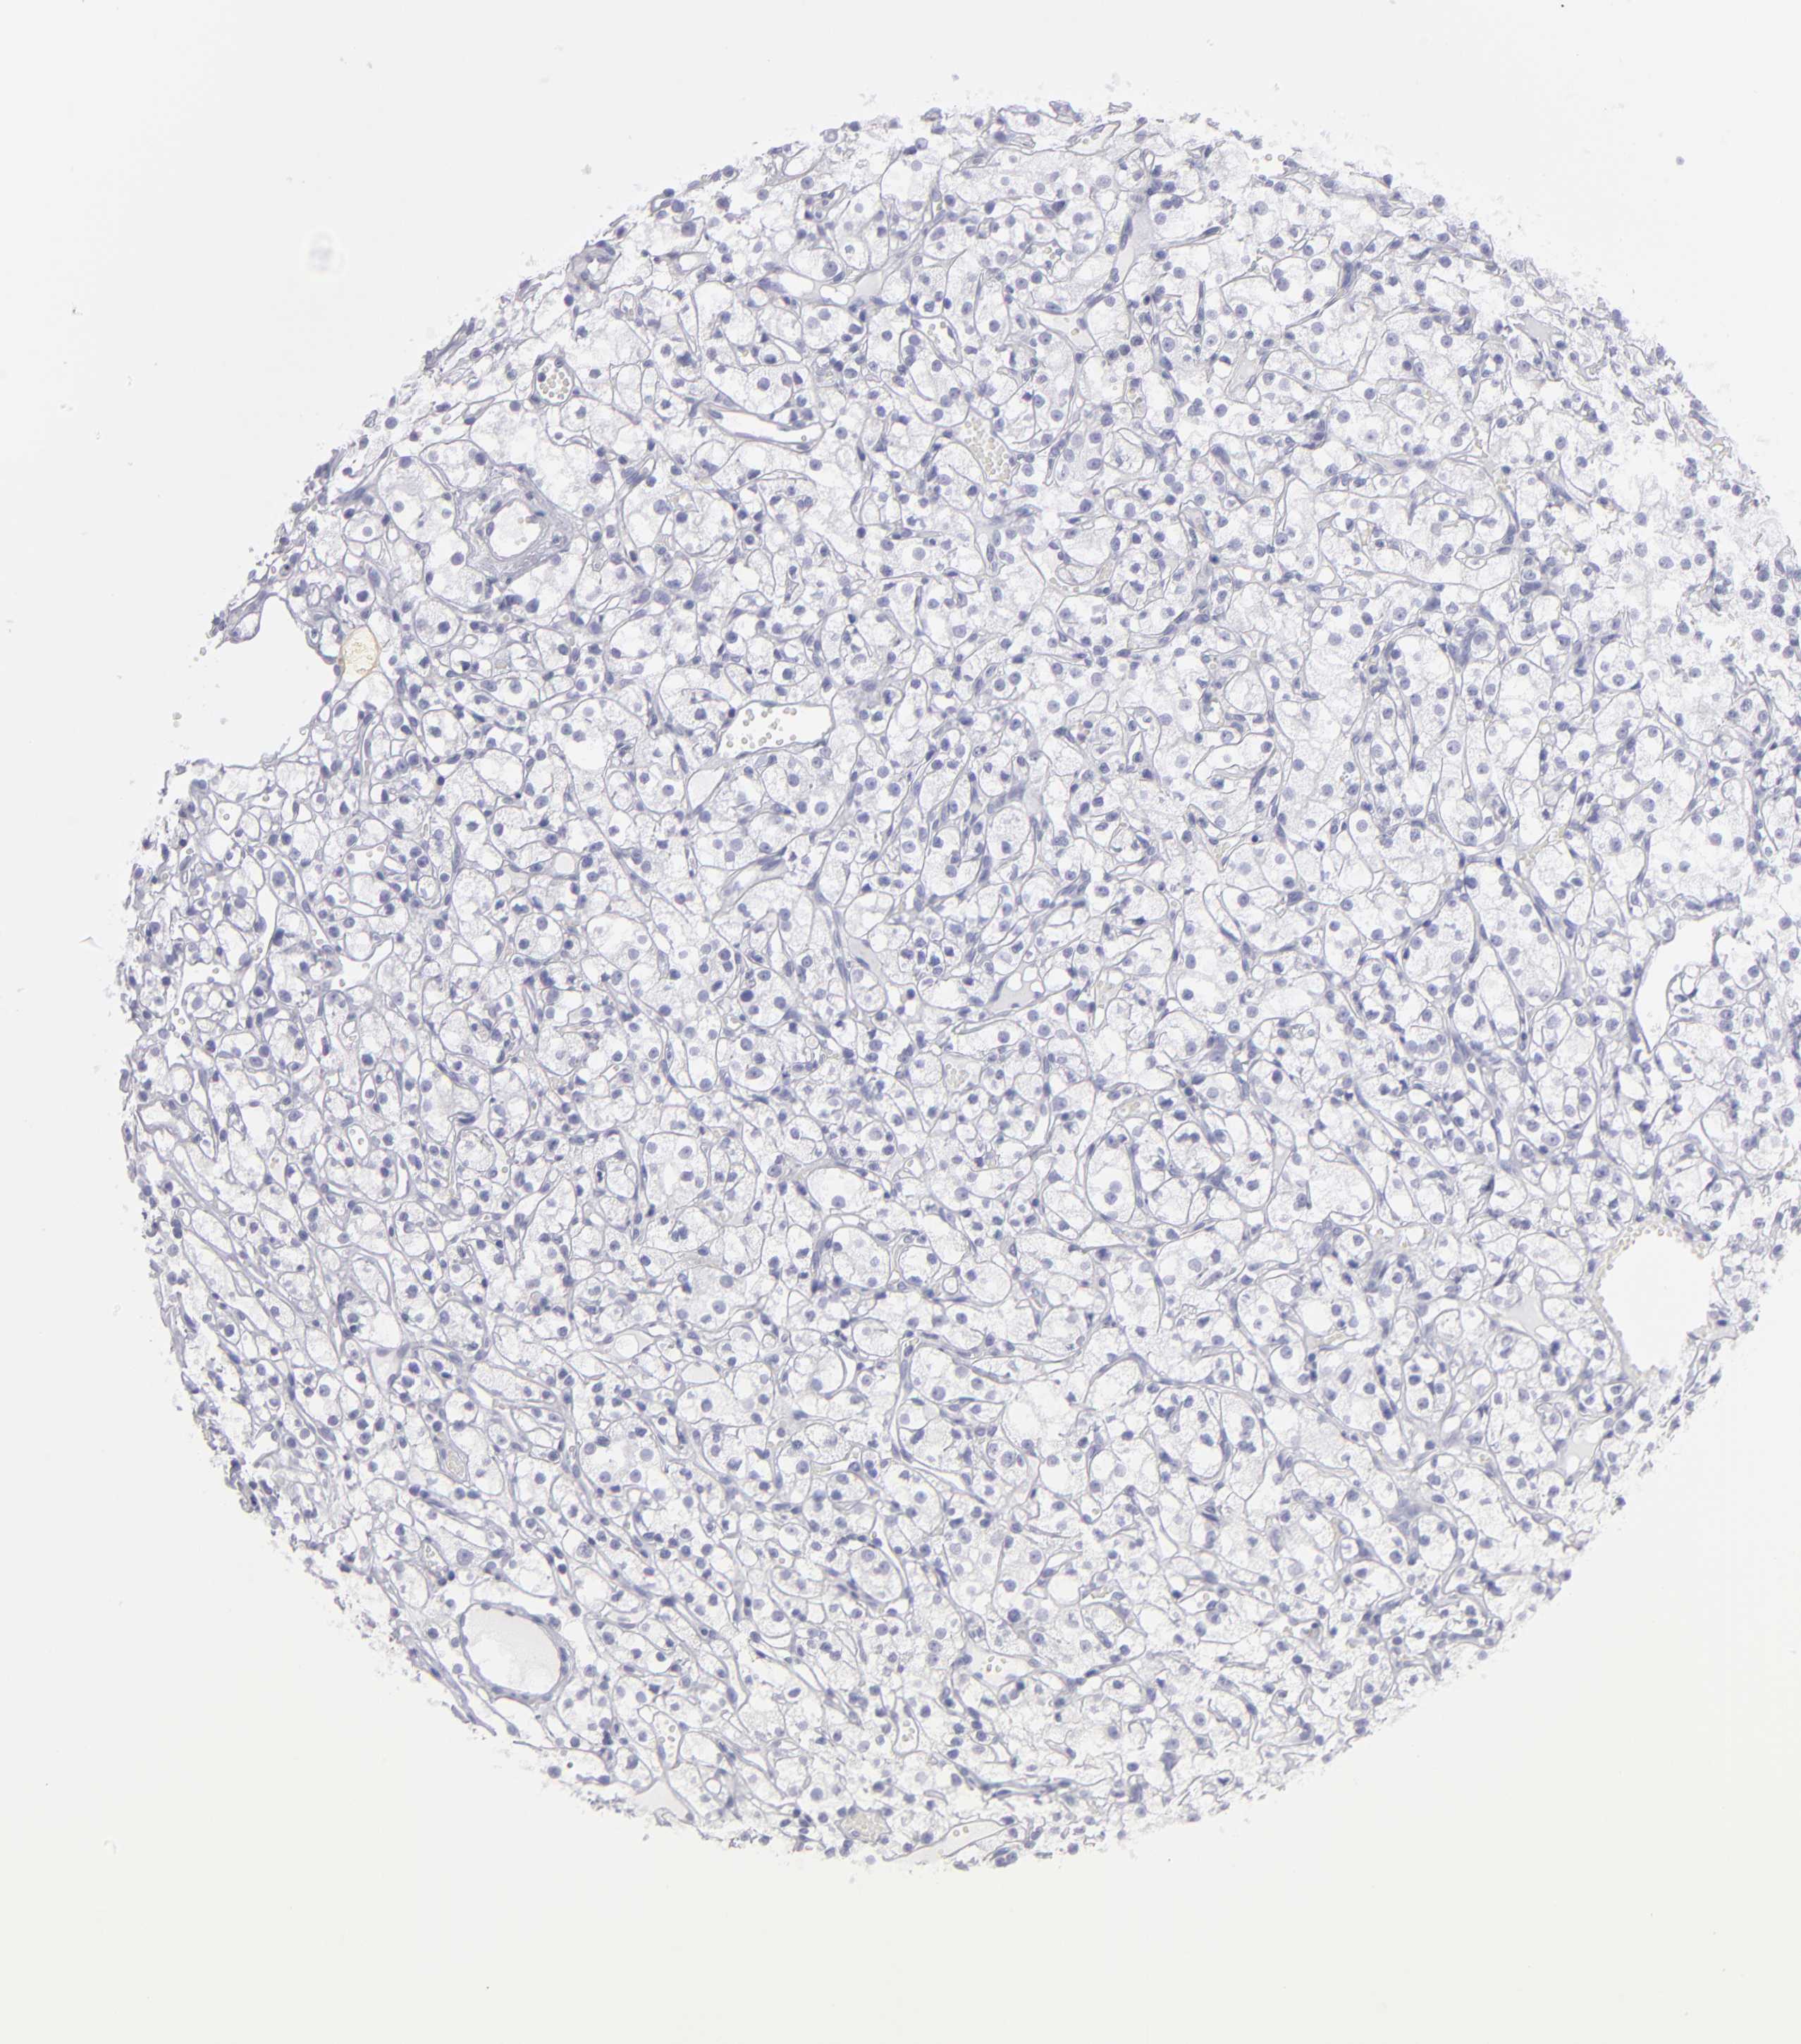

KIDNEY RENAL CLEAR CELL CARCINOMA (VALIDATION) - Interactive survival scatter ploti

The Survival Scatter plot shows the clinical status (i.e. dead or alive) for all individuals in the patient cohort, based on the same data that underlies the corresponding Kaplan-Meier plots. Patients that are alive at last time for follow-up are shown in blue and patients who have died during the study are shown in red.

The x-axis shows the expression levels (FPKM) of the investigated gene in the tumor tissue at the time of diagnosis. The y-axis shows the follow-up time after diagnosis (years). Both axes are complimented with kernel density curves demonstrating the data density over the axes. The top density plot shows the expression levels (FPKM) distribution among dead (red) and alive patients (blue). The right density plot shows the data density of the survived years of dead patients with high and low expression levels respectively, stratified using the cutoff indicated by the vertical dashed line through the Survival Scatter plot. This cutoff is automatically defined based on the FPKM cutoff that minimizes the p-score. The cutoff can be changed by dragging the vertical line or by entering a cutoff value in the square labeled "Current cut-off".

Under the Survival Scatter plot the p-score landscape (black curve; left axis) is shown together with dead median separation (red curve; right axis). Dead median separation is the difference in median mRNA expression between patients who have died with high and low expression, respectively. It is calculated as follows: median FPKM expression of dead patients with high expression - median FPKM expression of dead patients with low expression. This is intended to aid the user in visually exploring custom cutoffs and the associated p-scores and dead median separation.

Individual patient data is displayed and can be filtered by clicking on one or more of the category buttons on the top of the page. Categories describing expression level and patient information include: high, low, alive, dead, female, male and tumor stages. The scale of the x-axis can be toggled between linear and log-scale by clicking on the "x log" button. Mouse-over function shows TCGA ID, patient information and mRNA expression (FPKM) for each patient.

& Survival analysisi

Kaplan-Meier plots summarize results from analysis of correlation between mRNA expression level and patient survival. Patients were divided based on level of expression into one of the two groups "low" (under cut off) or "high" (over cut off). X-axis shows time for survival (years) and y-axis shows the probability of survival, where 1.0 corresponds to 100 percent.

ABCB1 is not prognostic in Kidney Renal Clear Cell Carcinoma (validation)

: 4.35

Average pTPM 22.5

Number of samples 100